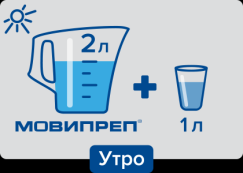

Одноэтапная утренняя подготовка.

Накануне исследования разрешены завтрак и обед (до 15:00) согласно списку разрешенных продуктов, а после 15:00 прием твердой пищи необходимо полностью исключить, при этом можно пить разрешенные жидкости в любом количестве.

В день исследования: 2 л раствора препарата Мовипреп принимаются утром в день обследования, после каждого принятого литра препарата Мовипреп необходимо выпить 500 мл воды (или чая); в завершающие 500 мл воды добавить пеногаситель симетикон в любой жидкой форме (не таблетки и не капсулы!) — ¼ флакона (эспумизан, боботик, сабсимплекс).